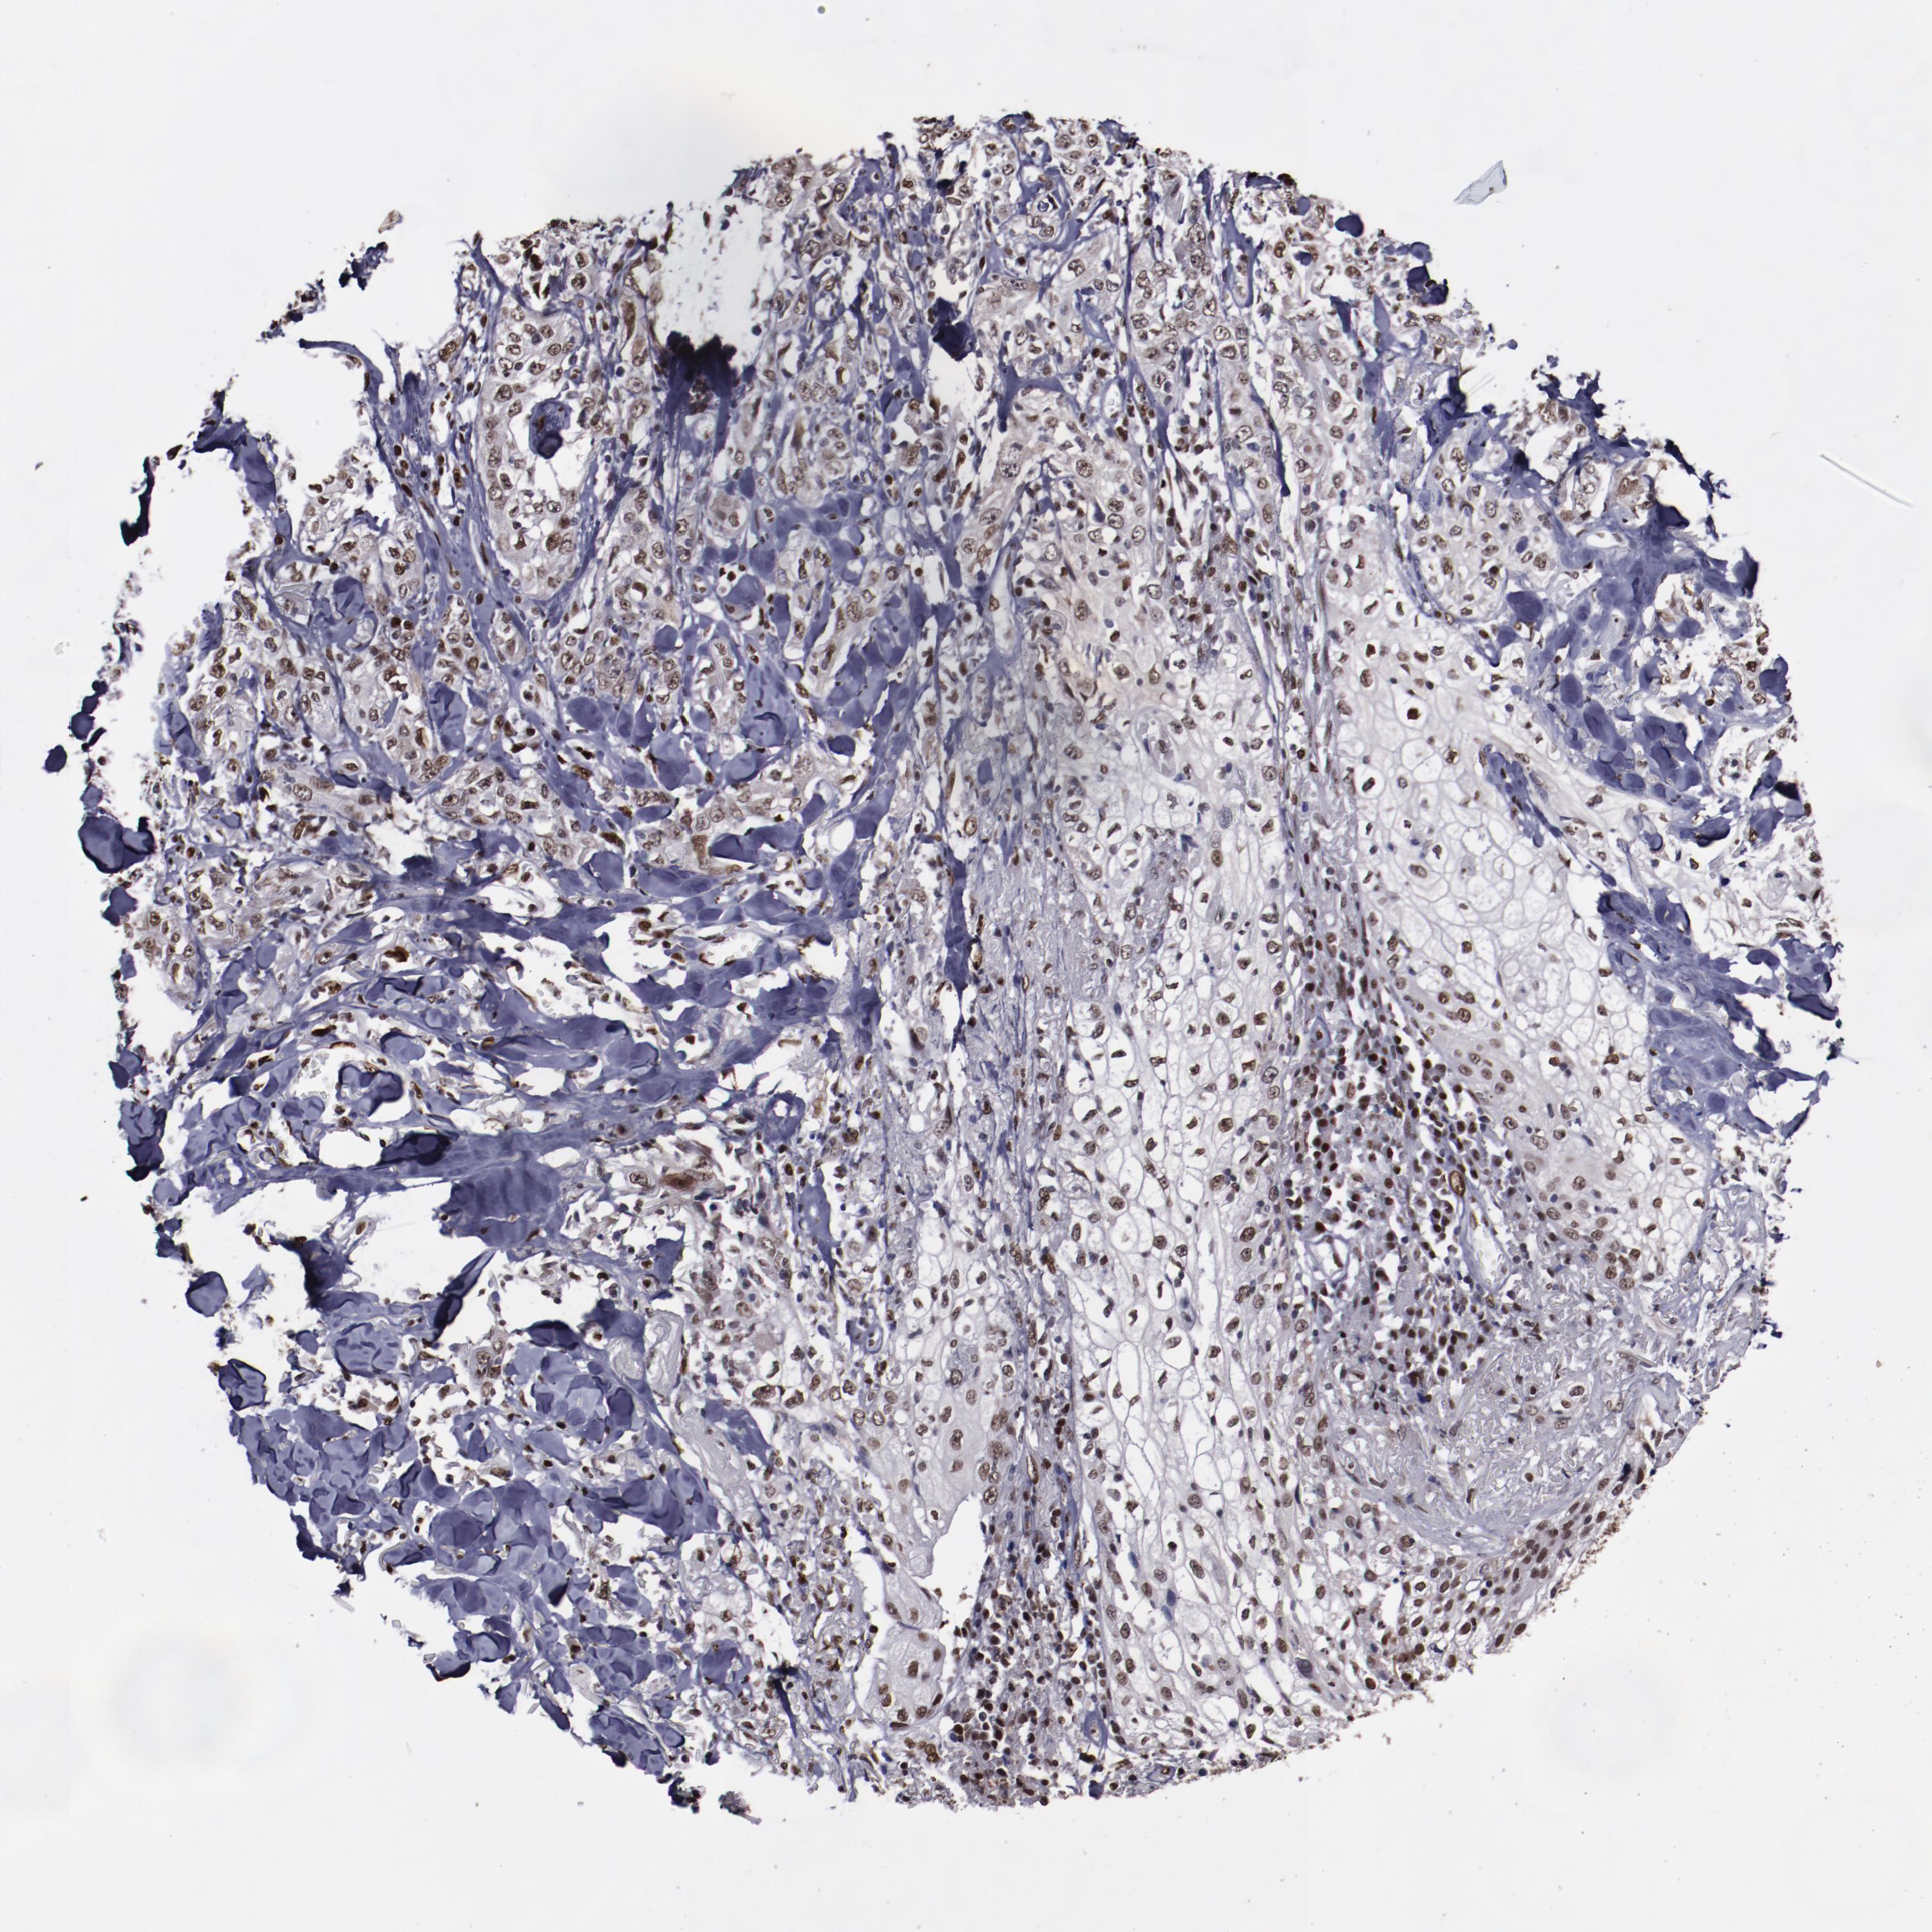

CANCER SKIN CANCER Show tissue menu

SKIN CANCER - Protein expressioni

A mouse-over function shows sample information and annotation data. Click on an image to view it in a full screen mode. Samples can be filtered based on level of antibody staining by selecting one or several of the following categories: high, medium, low and not detected. The assay and annotation is described here.

Each image is clickable and will lead to virtual microscopy that enables deeper exploration of all samples and also displays staining intensity scores, fraction scores and subcellular localization as well as patient and tissue information for each sample.

Antibody HPA002564

Antibody CAB004294

Antibody CAB047307

Staining

High

Medium

Low

Not detected

Intensity

Strong

Moderate

Weak

Negative

Quantity

>75%

75%-25%

<25%

None

Location

Nuclear

Cytoplasmic/membranous

Cytoplasmic/membranous,nuclear

Squamous cell carcinoma, NOS

Basal cell carcinoma

Squamous cell carcinoma, metastatic, NOS